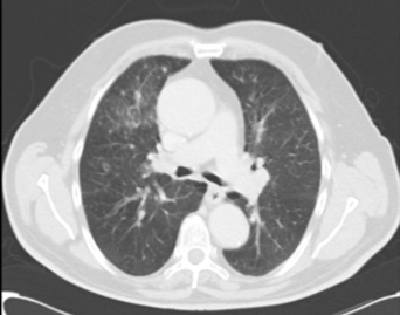

FIGURA 1: TAC CERVICOTORÁCICO: masa en tiroides (6x5x4 cm) con captación heterogénea de contraste que desplaza tráquea y esófago. Nódulos pulmonares subcentimétricos en ambos hemitórax.